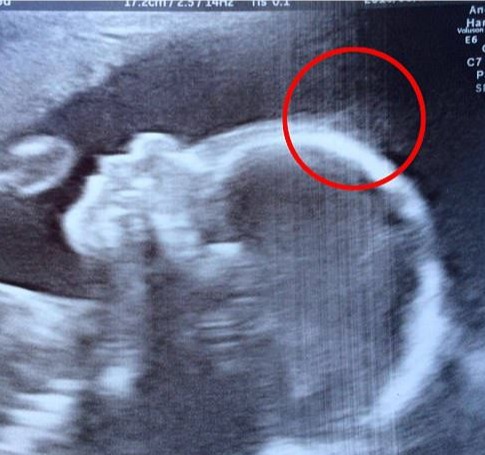

Már az ultrahangon is látszott a baba óriási hajkoronája. A szülőszobán viszont, amikor meglátták a fejét...

Natasha Gent igazi látványosságnak számít, ha kisbabájával sétálni indul, és ez persze egyáltalán nem véletlen....